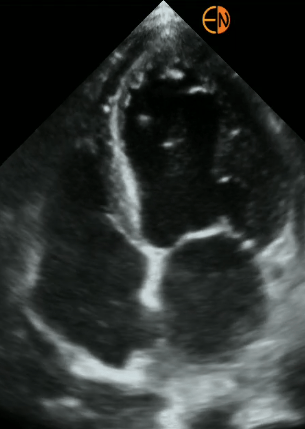

POCUS Cardíaco básico: Principais janelas cardíacas, avaliação da função sistólica dos ventrículos, avaliação do choque circulatório.

POCUS Cardíaco - medidas: Avaliação quantitativa do débito cardíaco, volume sistólico e função sistólica dos ventrículos.